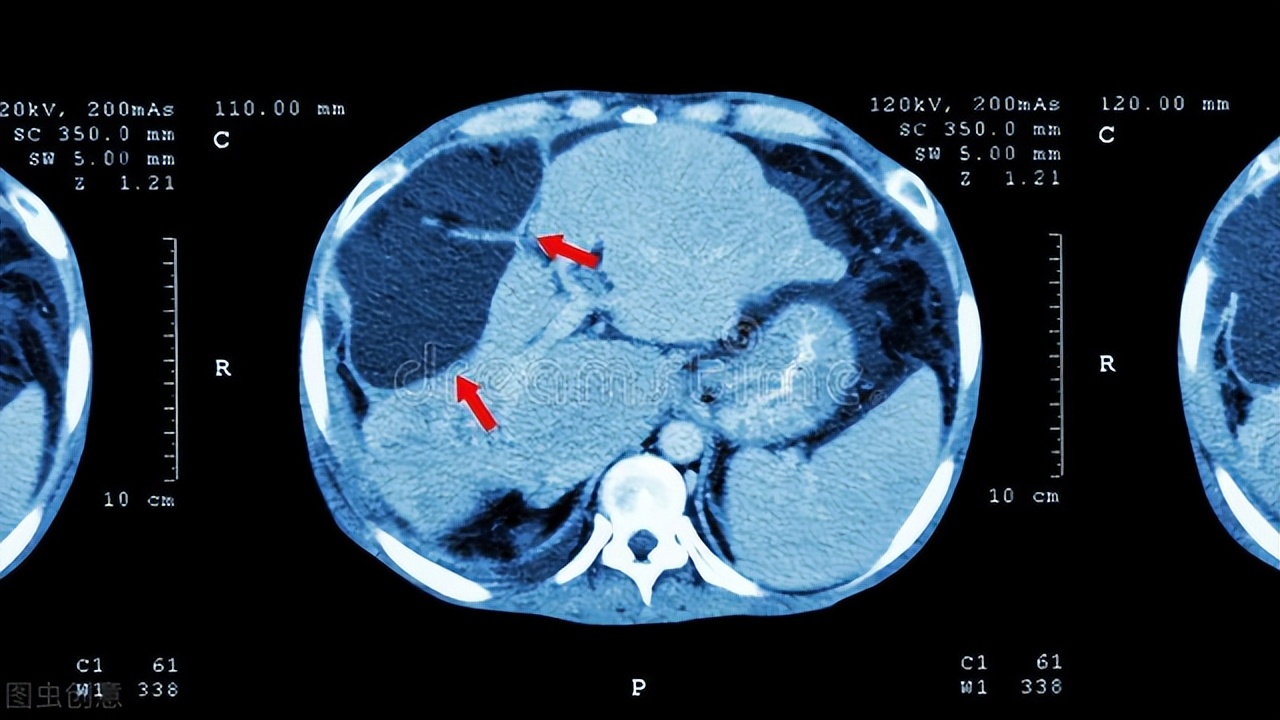

(3)靶区定位:建议采用CT和MRI图像融合技术,结合TACE后的碘油沉积来确定肝癌大体肿瘤的范围(GTV)。临床肿瘤体积(CTV)为GTV外加5 mm~10 mm, 计划体积(PTV)在使用ABC装置条件下为CTV外加6 mm。在没有使用ABC时更要根据患者的呼吸来确定。